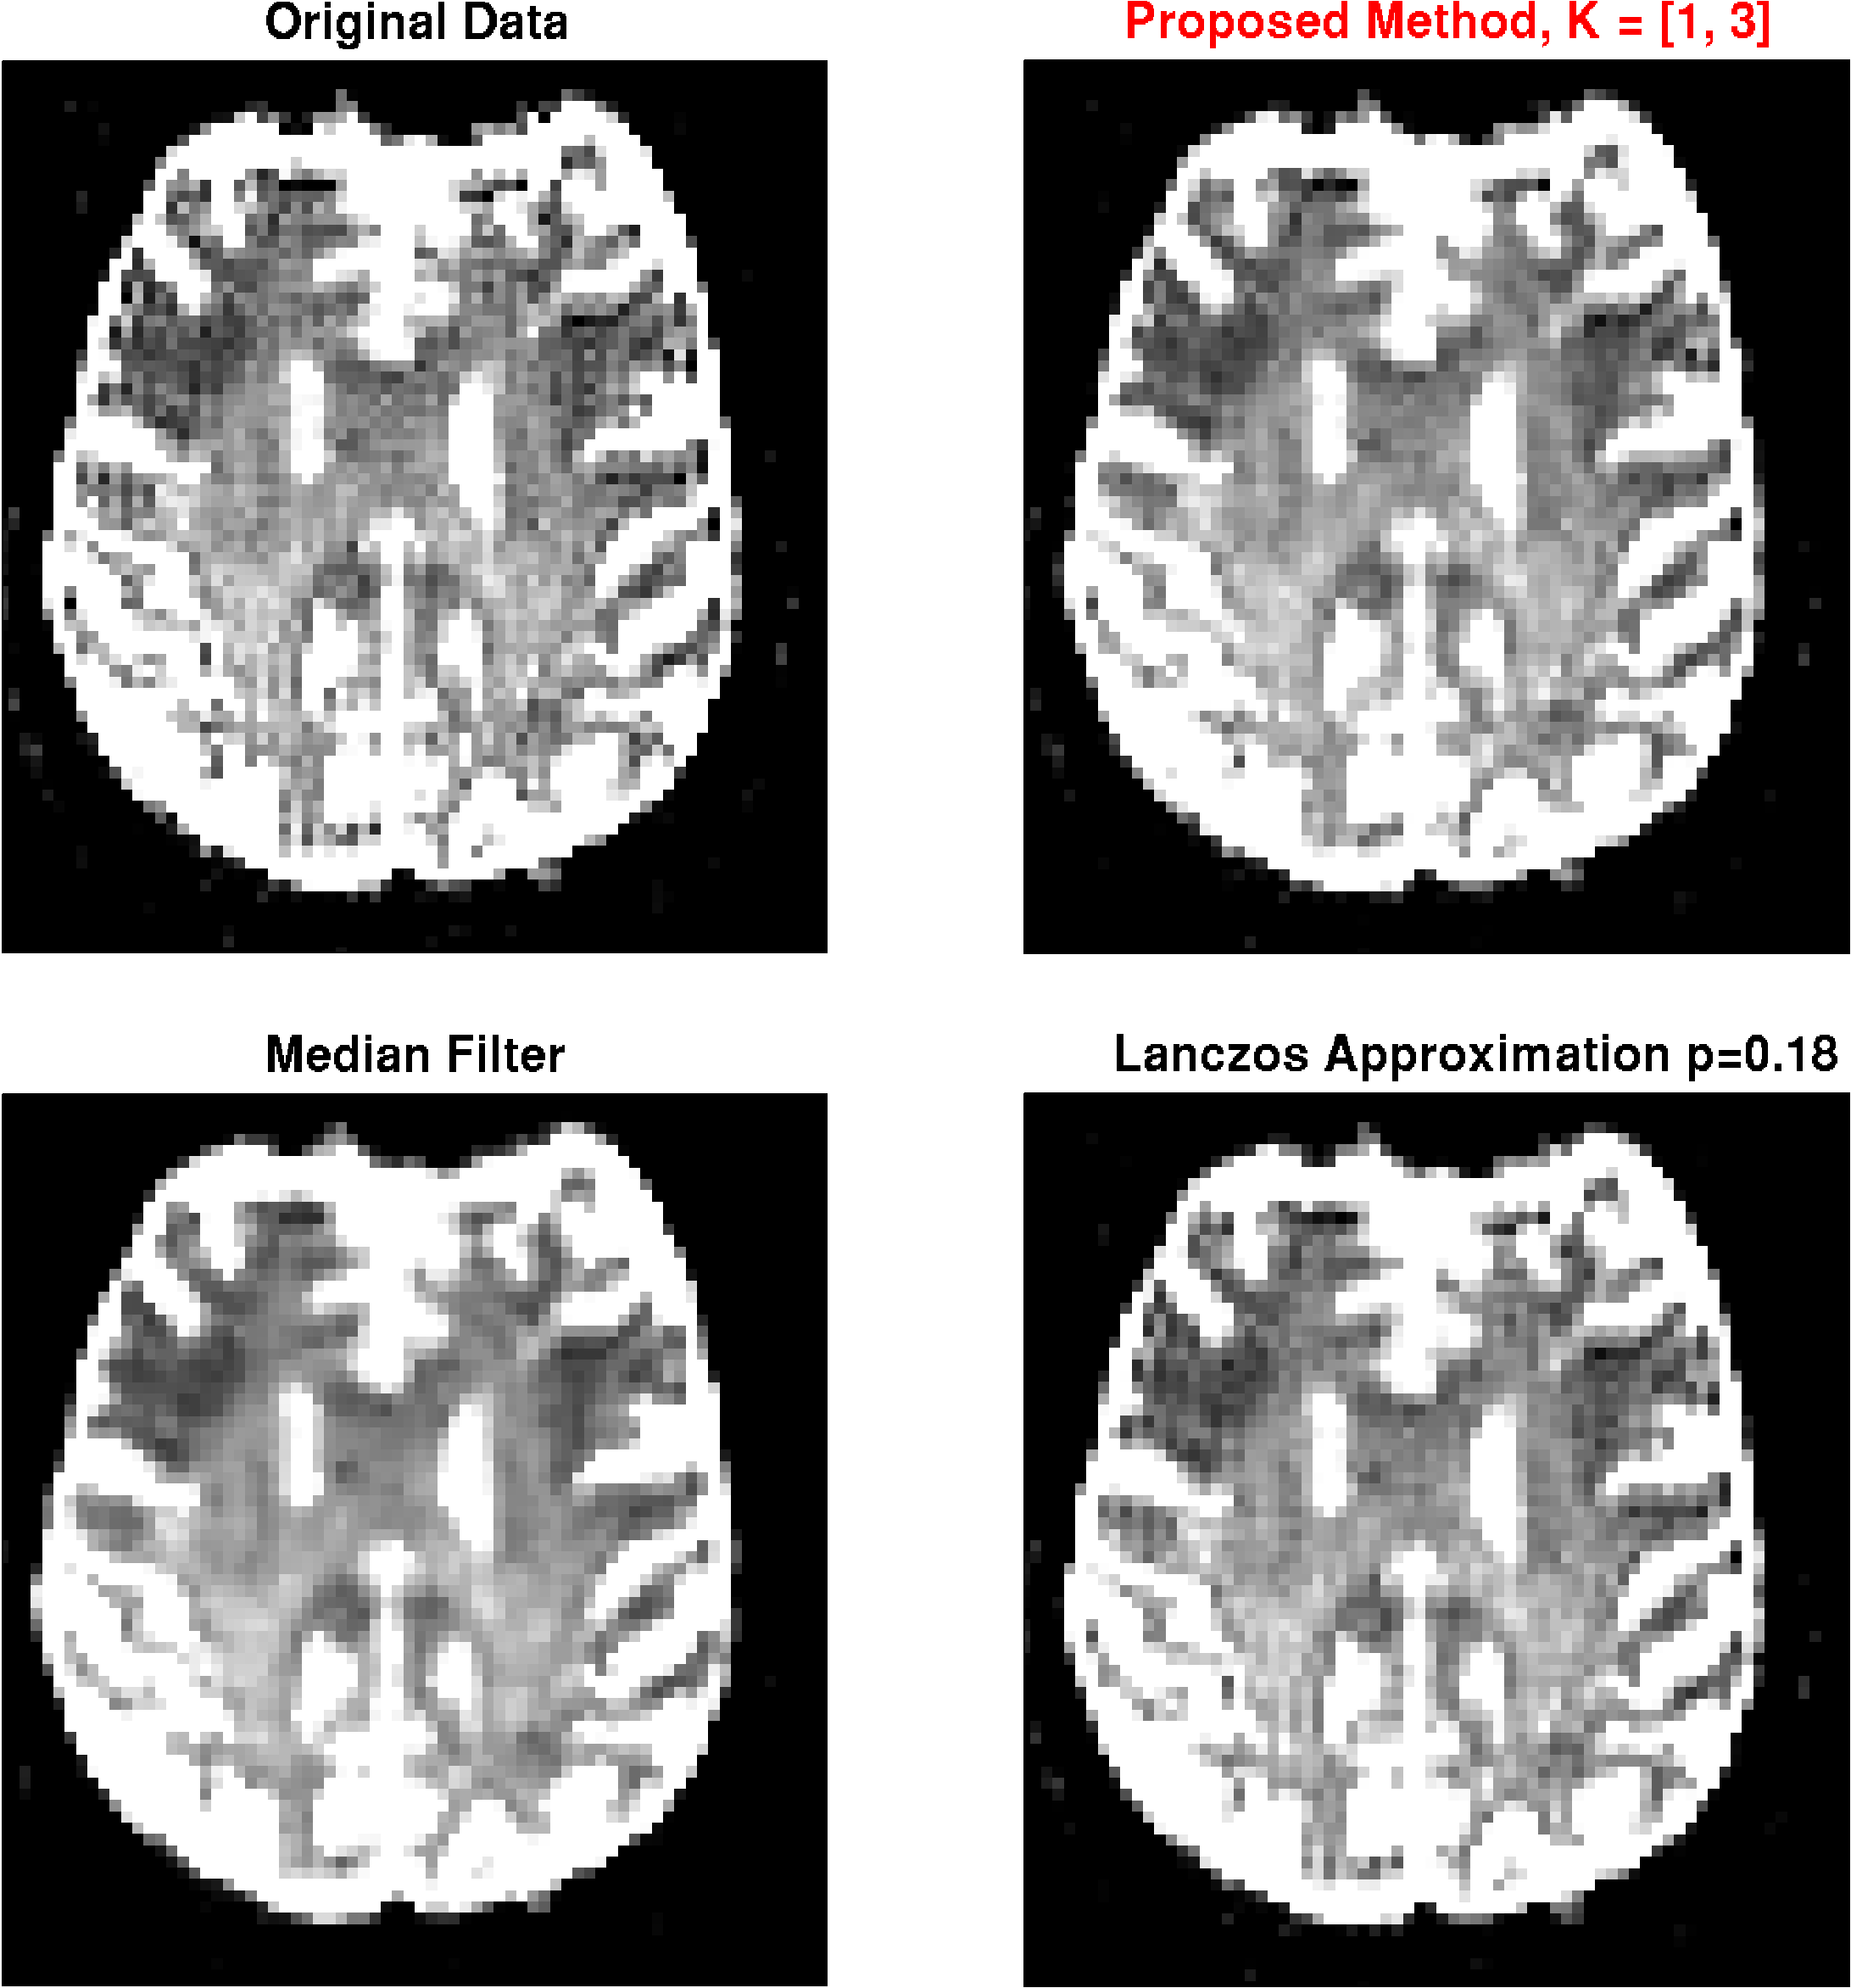

MRI Measurements

The method was applied to diffusion-weighted-images (DWI) with 70 directions, , using a gradient echo EPI sequence with , matrix size 104x104, resolution , performed on a 3T scanner (Siemens TIM TRIO, Siemens, Erlangen, Germany). No distortion correction was applied, as the involved correction methods already lead to significant filtering of the artifact, especially in phase direction. Due to the different image contrast for different -values, the artifact might even be amplified during post-processing of the diffusion parameters. Therefore, we also calculated diffusion maps, without and with artifact correction. We further applied the method to a -weighted image acquired with a turbo-spin-echo sequence, , resolution 1x1x5 on a 1.5T scanner (Siemens SONATA, Siemens, Erlangen, Germany). Both dataset were acquired in the context of clinical routine, written consent was obtained to use the data for scientific use.

MRI images

The results for DWI measurements are shown for one slice in Fig. 6. Apparently, the -images exhibit strong ringing artifacts, which is even more emphasized after diffusion calculation. The artifact can be reduced with both, the median filter and the Lanczos approximation with , however, at the cost of strong smoothing. With the proposed method on the other hand, the artifact can virtually completely be removed with minimal filtering. Results from the -weighted image given in Fig. 7. The findings are basically the same as for the DWI measurement.

b=0 images Radial diffusivity